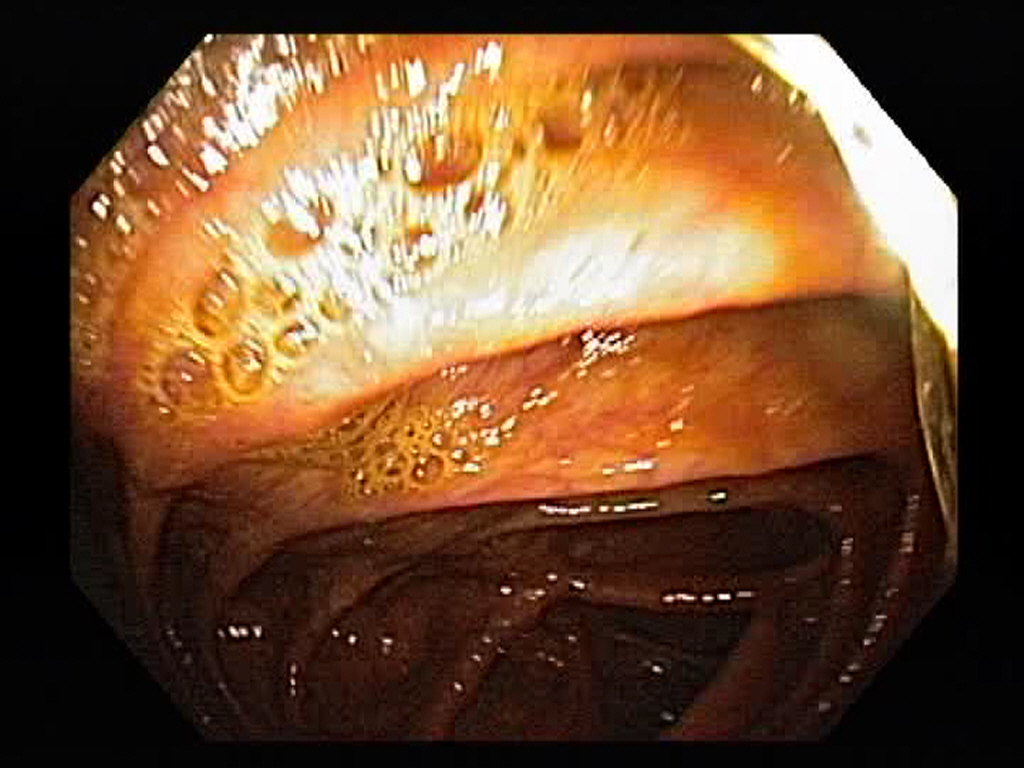

Normal Ascending Colon